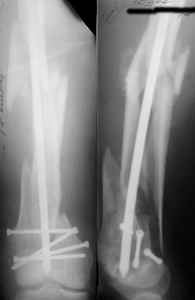

Attached are few examples from our Hospital:

A. Difficult reductions, even in retrograde nailing (my preference, easier control of "small" distal fragment) and it is much, much harder to do it anterograde (Alex, do you have one good case in your collection of anterograde nailing in very distal fractures - as you have suggested that I

should have done it in my previously posted case?

Malpositioning is much too common (recurvatum, varus - valgus).

B. Fixation loosening: distal cutting of the nail, non-unions do happen (cases attached).